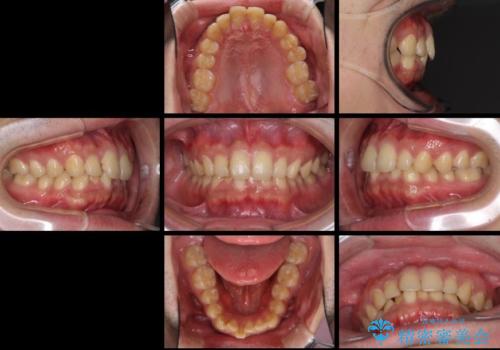

深い咬み合わせと前歯のデコボコの改善 インビザラインによる矯正治療

- 上下前歯のデコボコと下の前歯が隠れるほどの深い咬み合わせを気にして来院された患者様です。

インビザラインによる上下歯列の拡大と、IPR(歯と歯の間を削る)にるスペースの獲得により、口元のデコボコとディープバイトを改善することとしました。

デコボコがなくなったことで日頃の清掃が行いやすくなり、深い咬み合わせが改善したことで、食いしばりによる顎の負担も軽減されました。